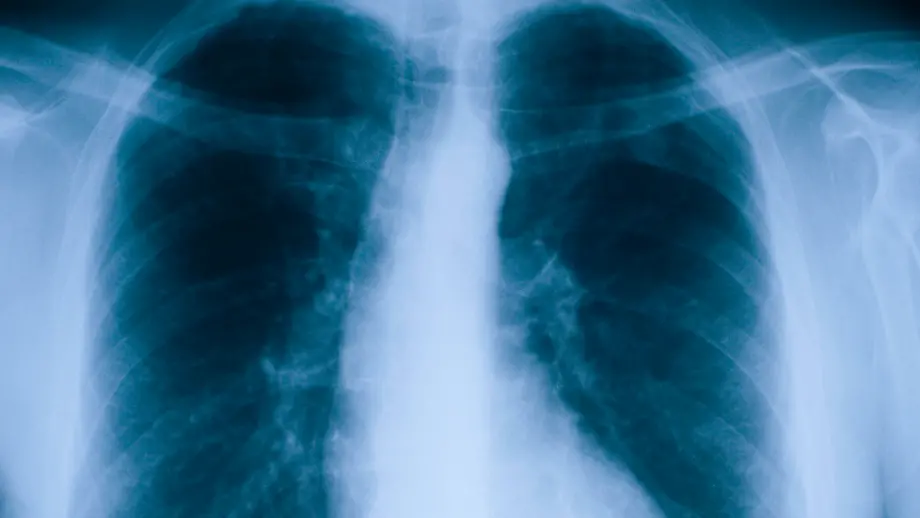

19.12.2025, 14:14 UhrNach Jahren mit Lungenfibrose verschlechtert sich der Gesundheitszustand der norwegischen Kronprinzessin Mette-Marit Tjessem Høiby deutlich. Die 52-Jährige muss sich nun einer Organtransplantation unterziehen. Arzt und Medizinjournalist Dr. Christoph Specht erklärt die Krankheit.